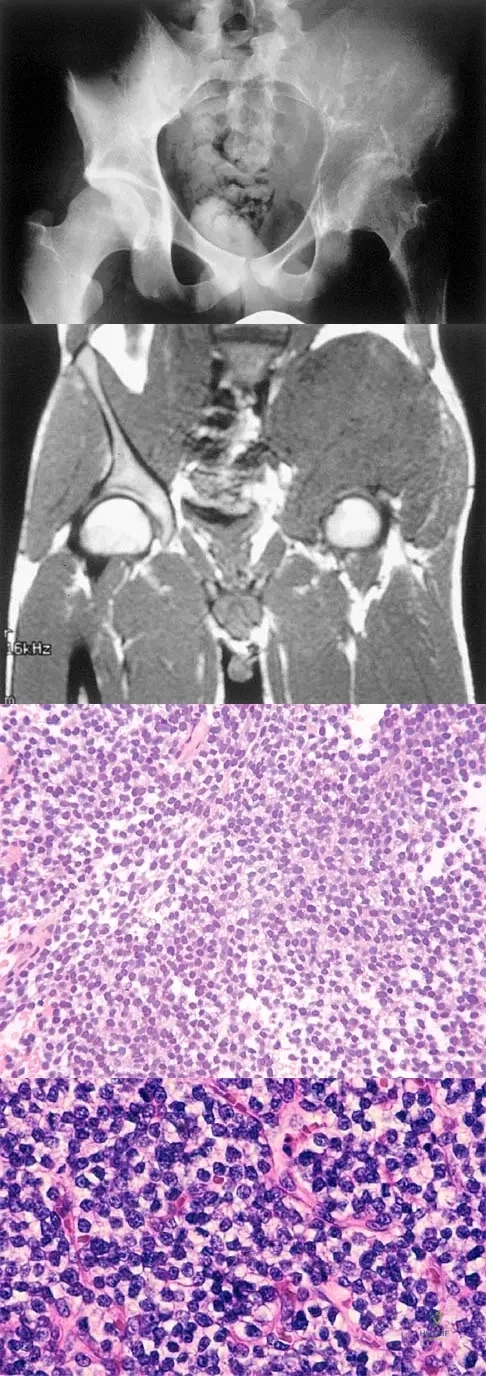

A 25-year-old man has had an insidious onset of left hip pain over the past 11 months. A radiograph, coronal MRI scan, and histopathologic specimens are seen in Figures 2a through 2d. What is the most likely diagnosis?

Explanation